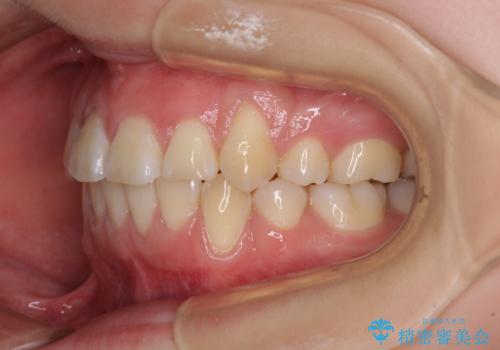

歯列はきれいに整いますが、歯肉ラインは治療前の歯肉の位置を踏襲します。

特に八重歯であった歯は歯冠が長く見えますので、改善を希望される場合には、歯肉移植術を行う必要があります。